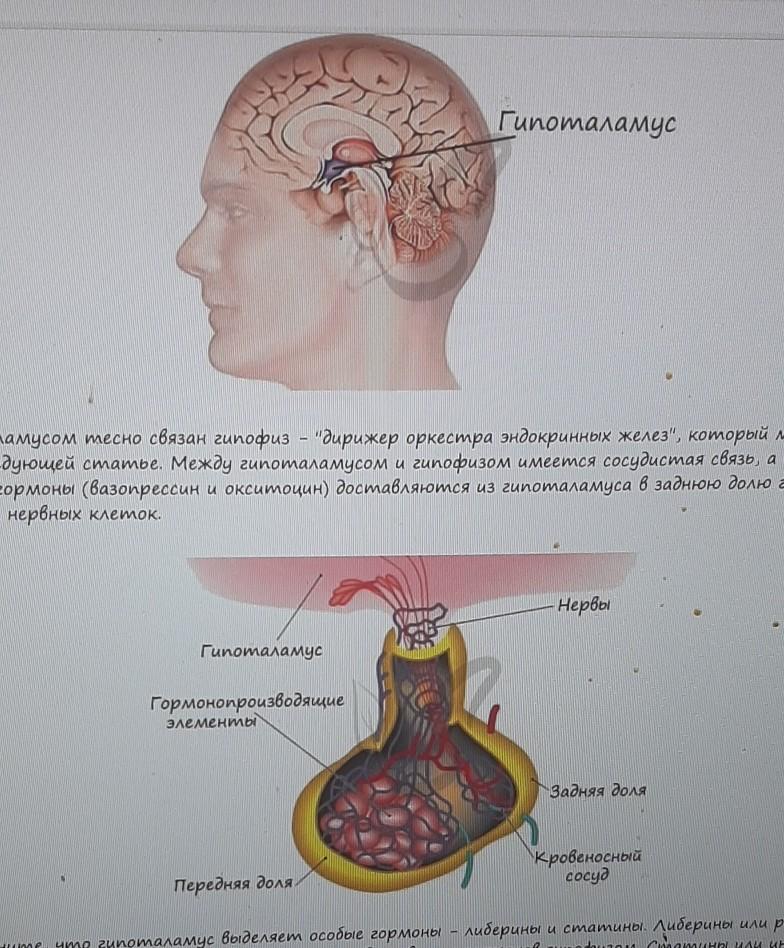

Как работает центр насыщения в гипоталамусе: визуальные иллюстрации